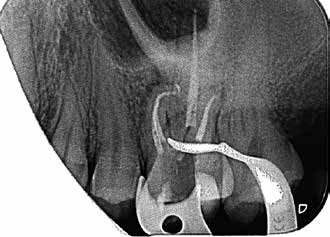

Bei der Diagnose des schmerzfreien Patienten stellte sich die beschriebene Erhebung schließlich als Fistel heraus (Abb. 1). Der Zahn 26 sowie die Nachbarzähne wurden zunächst einer Sensibilitätsprüfung unterzogen, wobei der Kältetest an Zahn 26 negativ ausfiel. Im Anschluss erfolgte dann die Anfertigung der diagnostischen Röntgenaufnahmen (Abb. 2 und 3). Dazu wurde ein Guttapercha-Stift in den Fistelgang eingebracht, um die Lokalisation der Entzündung zu erleichtern. Speziell bei der distal exzentrischen Aufnahme ließ sich dabei an 2 Wurzelspitzen des Zahns 26 die Entzündung ausmachen (Abb. 2). Insofern war in diesem Fall eine endodontische Behandlung des Zahnes angezeigt. Für diese wurde sogleich ein Folgetermin vereinbart.

Als sich der Patient immer noch schmerzfrei 4 Wochen später im Rahmen des Termins zur definitiven Versorgung in der Praxis vorstellte, war lediglich noch das Fistelmaul, aber keine Erhebung am Zahnfleisch mehr zu sehen (Abb. 4). Nachdem auch sonst keine Auffälligkeiten festzustellen waren, wurde wie geplant mit der endgültigen Versorgung des Zahnes 26 begonnen. Hierfür wurde zunächst eine Isolierung des Zahnes mit Kofferdam vorgenommen (Abb. 5). Für ein genaueres Bild vom Verlauf der Wurzelkanalanatomie lieferte eine Kontrastaufnahme mithilfe von K-Feilen und eines Silberstiftes, mb2, (Abb. 6) die notwendigen Informationen. Dabei stellte sich heraus, dass insbesondere einer der Kanäle sich durch eine außerordentliche Krümmung von beinahe 90° auszeichnete (Abb. 7).